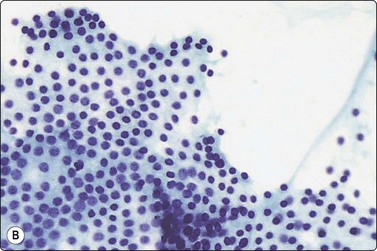

image image

Fig. 6.18 Follicular neoplasm

Cellular smears of single cells, microfollicles or rosettes in a repetitive manner; benign adenoma by histology (A, MGG, HP; B, Pap, HP).

Fig. 6.19 Follicular neoplasm

Smears very similar to Figure 6.18; follicular carcinoma with vascular invasion by histology (A, MGG, HP; B, Pap, HP).

FNs are classified as benign (FA) and malignant (FC). FAs and most FCs are encapsulated tumors, occurring in one of the lobes. Histological diagnosis of a well-differentiated FC requires demonstration of capsular and/or vascular permeation. Most FNs, especially adenomas, have a uniform internal structure that is reflected in the cytological smears. FAs are more common in women and microscopically show a variety of histological patterns such as microfollicular (fetal), normofollicular, macrofollicular, trabecular, solid (embryonal), Hurthle cell and atypical adenomas.42 Cytologically, follicular lesions include FA, FC, cellular NG and FV-PC.121

Smears in FN are cellular in a bloody background that is usually devoid of colloid. Many uniform-sized follicular cell clusters, microfollicles and rosette formations are present. Syncytial aggregates, nuclear crowding and overlapping are also often seen.

The repetitive smear pattern with uniform cell population is in contrast to the variable pattern of different cell types seen in colloid and hyperplastic nodules. Microacinar clusters with a central lumen (that may contain a drop of colloid) represent microfollicles (Figs 6.18, 6.19 and 6.21B). These are characteristic of FN but may be found focally in NG. Rosette-like groupings without a lumen (Fig. 6.20) suggest a more solid growth pattern. A trabecular pattern is represented by rows and elongated aggregates of epithelial cells that resemble papillary structures when they adhere to strands of vascular stroma (see Fig. 6.33B,C). Small blood vessels with adherent epithelial cells can be found in any type of follicular neoplasm (see Fig. 6.25A).